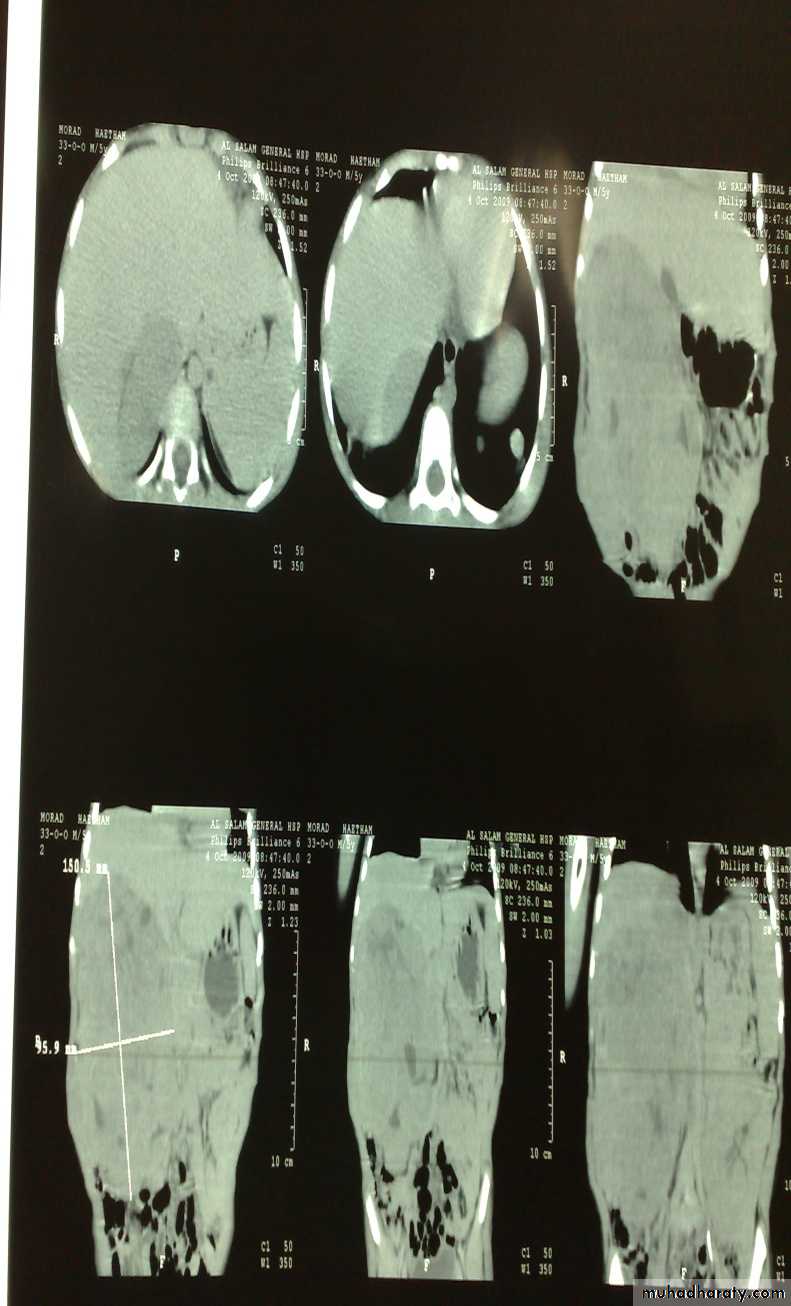

The Child with an Abdominal Mass

5 years child, presented with mass in the flank.

Dx: nephroblastomaDDx of mass in the flank:

1- Wilms tumor2- Neuroblastoma

3- Neglected PUJ obstruction

Presentation:

1- Mass2- hematuria

3- hypertension(1/3pt)

4-Incidental finding

Treatment by surgery remove the kidney + chemotherapy

The most common of pediatric renal tumor is Wilms tumor(second is neuroblastoma) (third is lymphoma non-hogkins),Neuroblastoma in the adrenal gland

Presenation : abd. Pain & mass &HT &incidental finding &recon eyeDansing eye syndrome

-diarrhea &flushing bz of catecolamines secreted

Dx: by fenyl mandilic acid in urine

Sites ;1-mediastinum2-Abd. Mass2/3 (supra-renal)

3-cervical

4-Pelvic